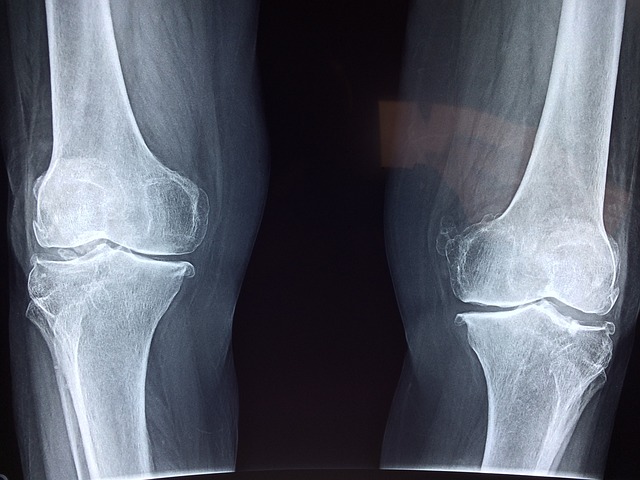

3) 잦은 골절

특히 엉덩이, 손목, 척추의 뼈는 사소한 넘어짐이나 약간의 충격에도 쉽게 부러질 수 있습니다.